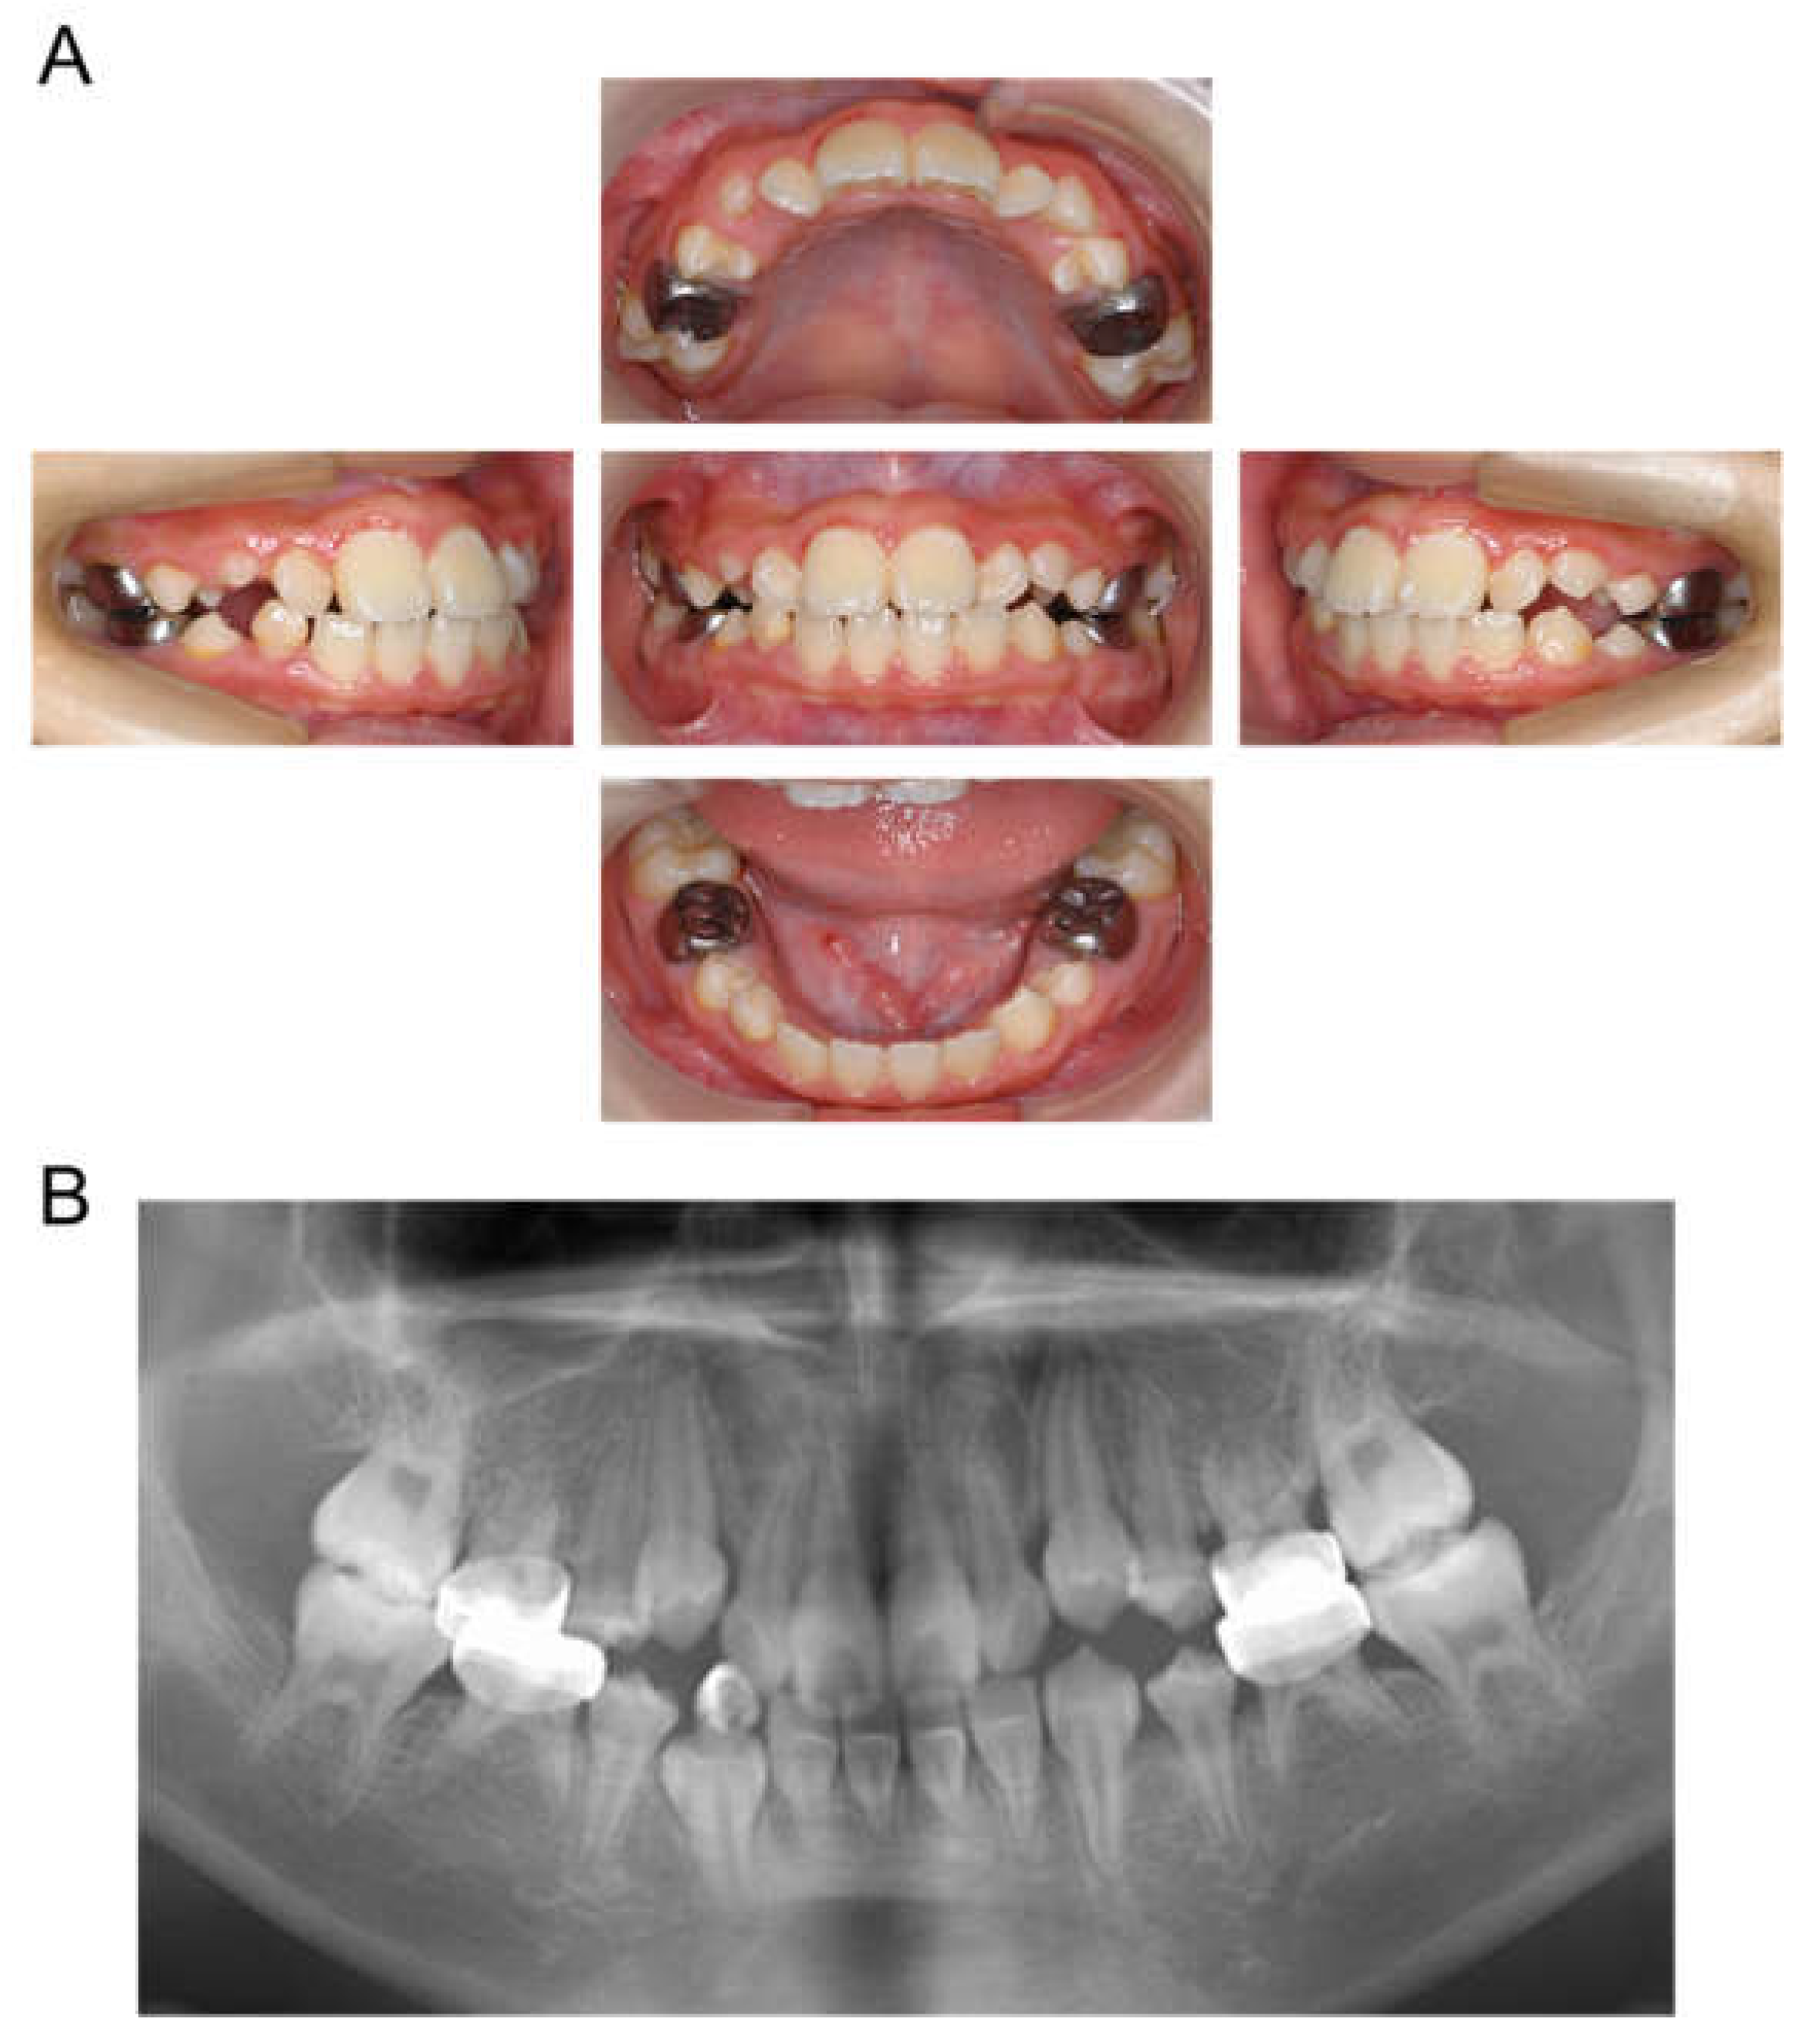

| Tooth | Diagnosis | Final Restoration |

|---|---|---|

| Maxilla | ||

| 51 | C2 | Resin-based composite crown |

| 52 | C2 | Resin-based composite crown |

| 53 | C2 | Resin filling |

| 54 | C2 | Preformed stainless-steel crown |

| 55 | C2 | Preformed stainless-steel crown |

| 61 | C2 | Resin-based composite crown |

| 62 | C2 | Resin-based composite crown |

| 63 | C2 | Resin filling |

| 64 | C2 | Preformed stainless-steel crown |

| 65 | C2 | Preformed stainless-steel crown |

| Mandible | ||

| 71 | C2 | No treatment |

| 72 | C2 | Resin filling |

| 73 | C2 | Resin filling |

| 74 | C2 | Preformed stainless-steel crown |

| 75 | C2 | Preformed stainless-steel crown |

| 81 | C2 | No treatment |

| 82 | C2 | Resin filling |

| 83 | C2 | Resin filling |

| 84 | C2 | Preformed stainless-steel crown |

| 85 | C2 | Preformed stainless-steel crown |